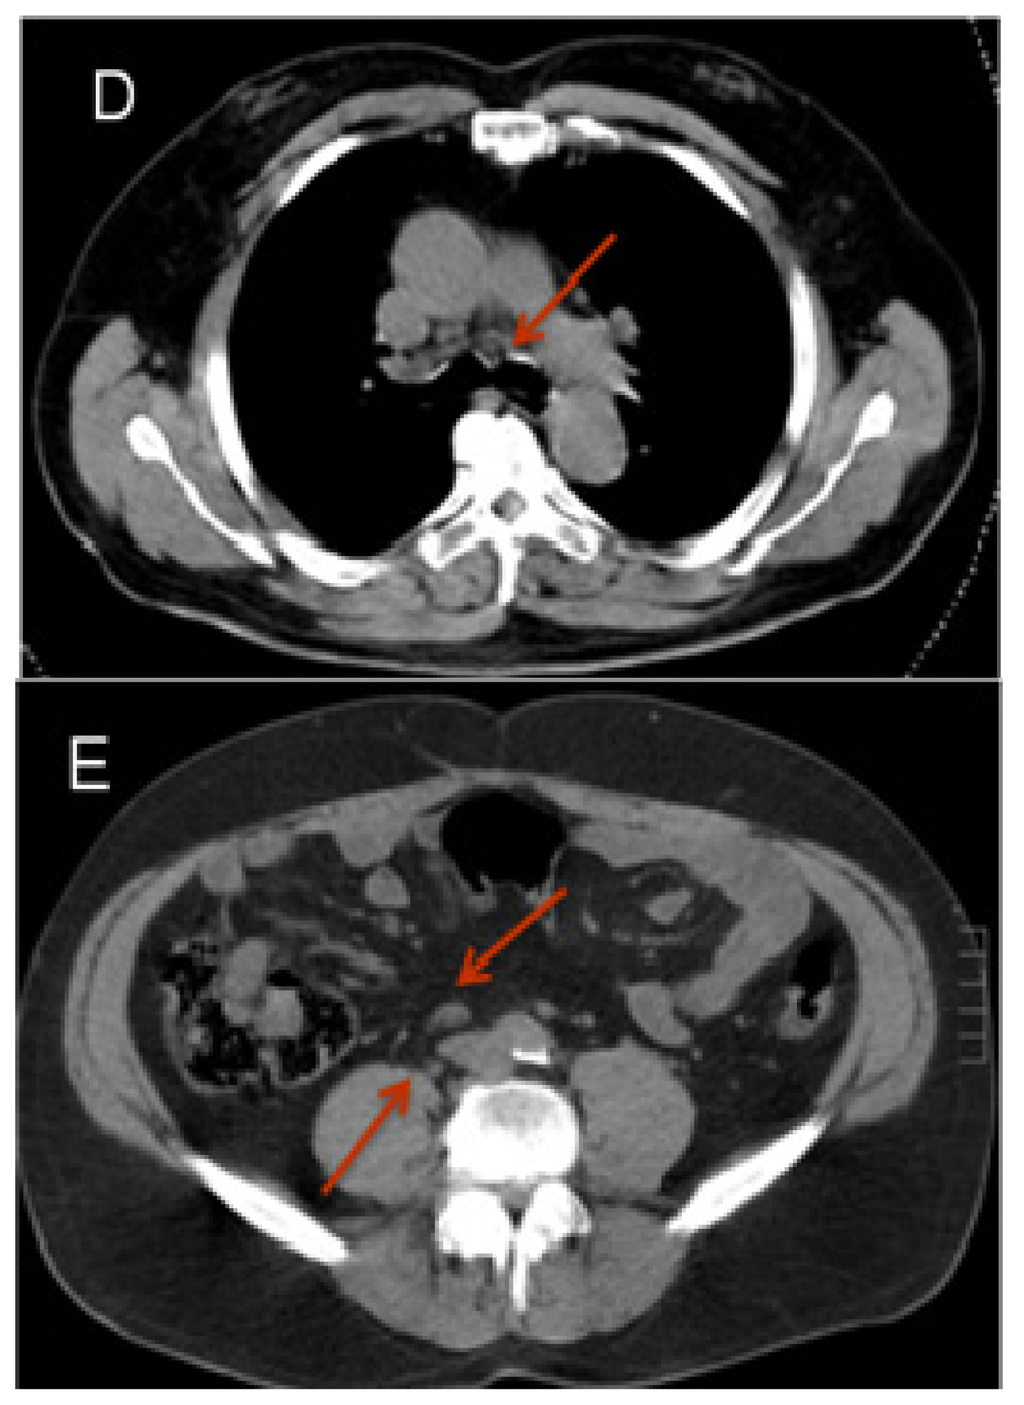

Figure 1.

18F-choline PET-CT. Patient after radical prostatectomy with slowly increasing PSA (current PSA: 1.5 μg/L). The figure shows series of native CT images (A); PET images 60 min after the administration of 18F-choline (B) and fused PET-CT images (C) in transversal, sagittal and coronal views. The PET images show a small hot spot in the right inguinal region with increased isotope uptake. In the PET-CT fused images this spot can be identified as a small right inguinal lymph node highly suspect for a metastasis. (F: Transverse plane; L: Saggital plane; A: Coronal plane).